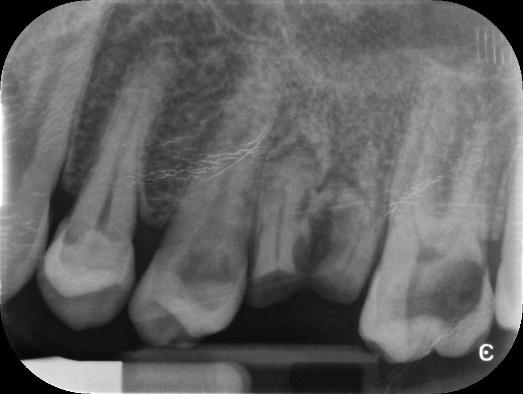

Lower Molar and premolar Primary root canal treatment